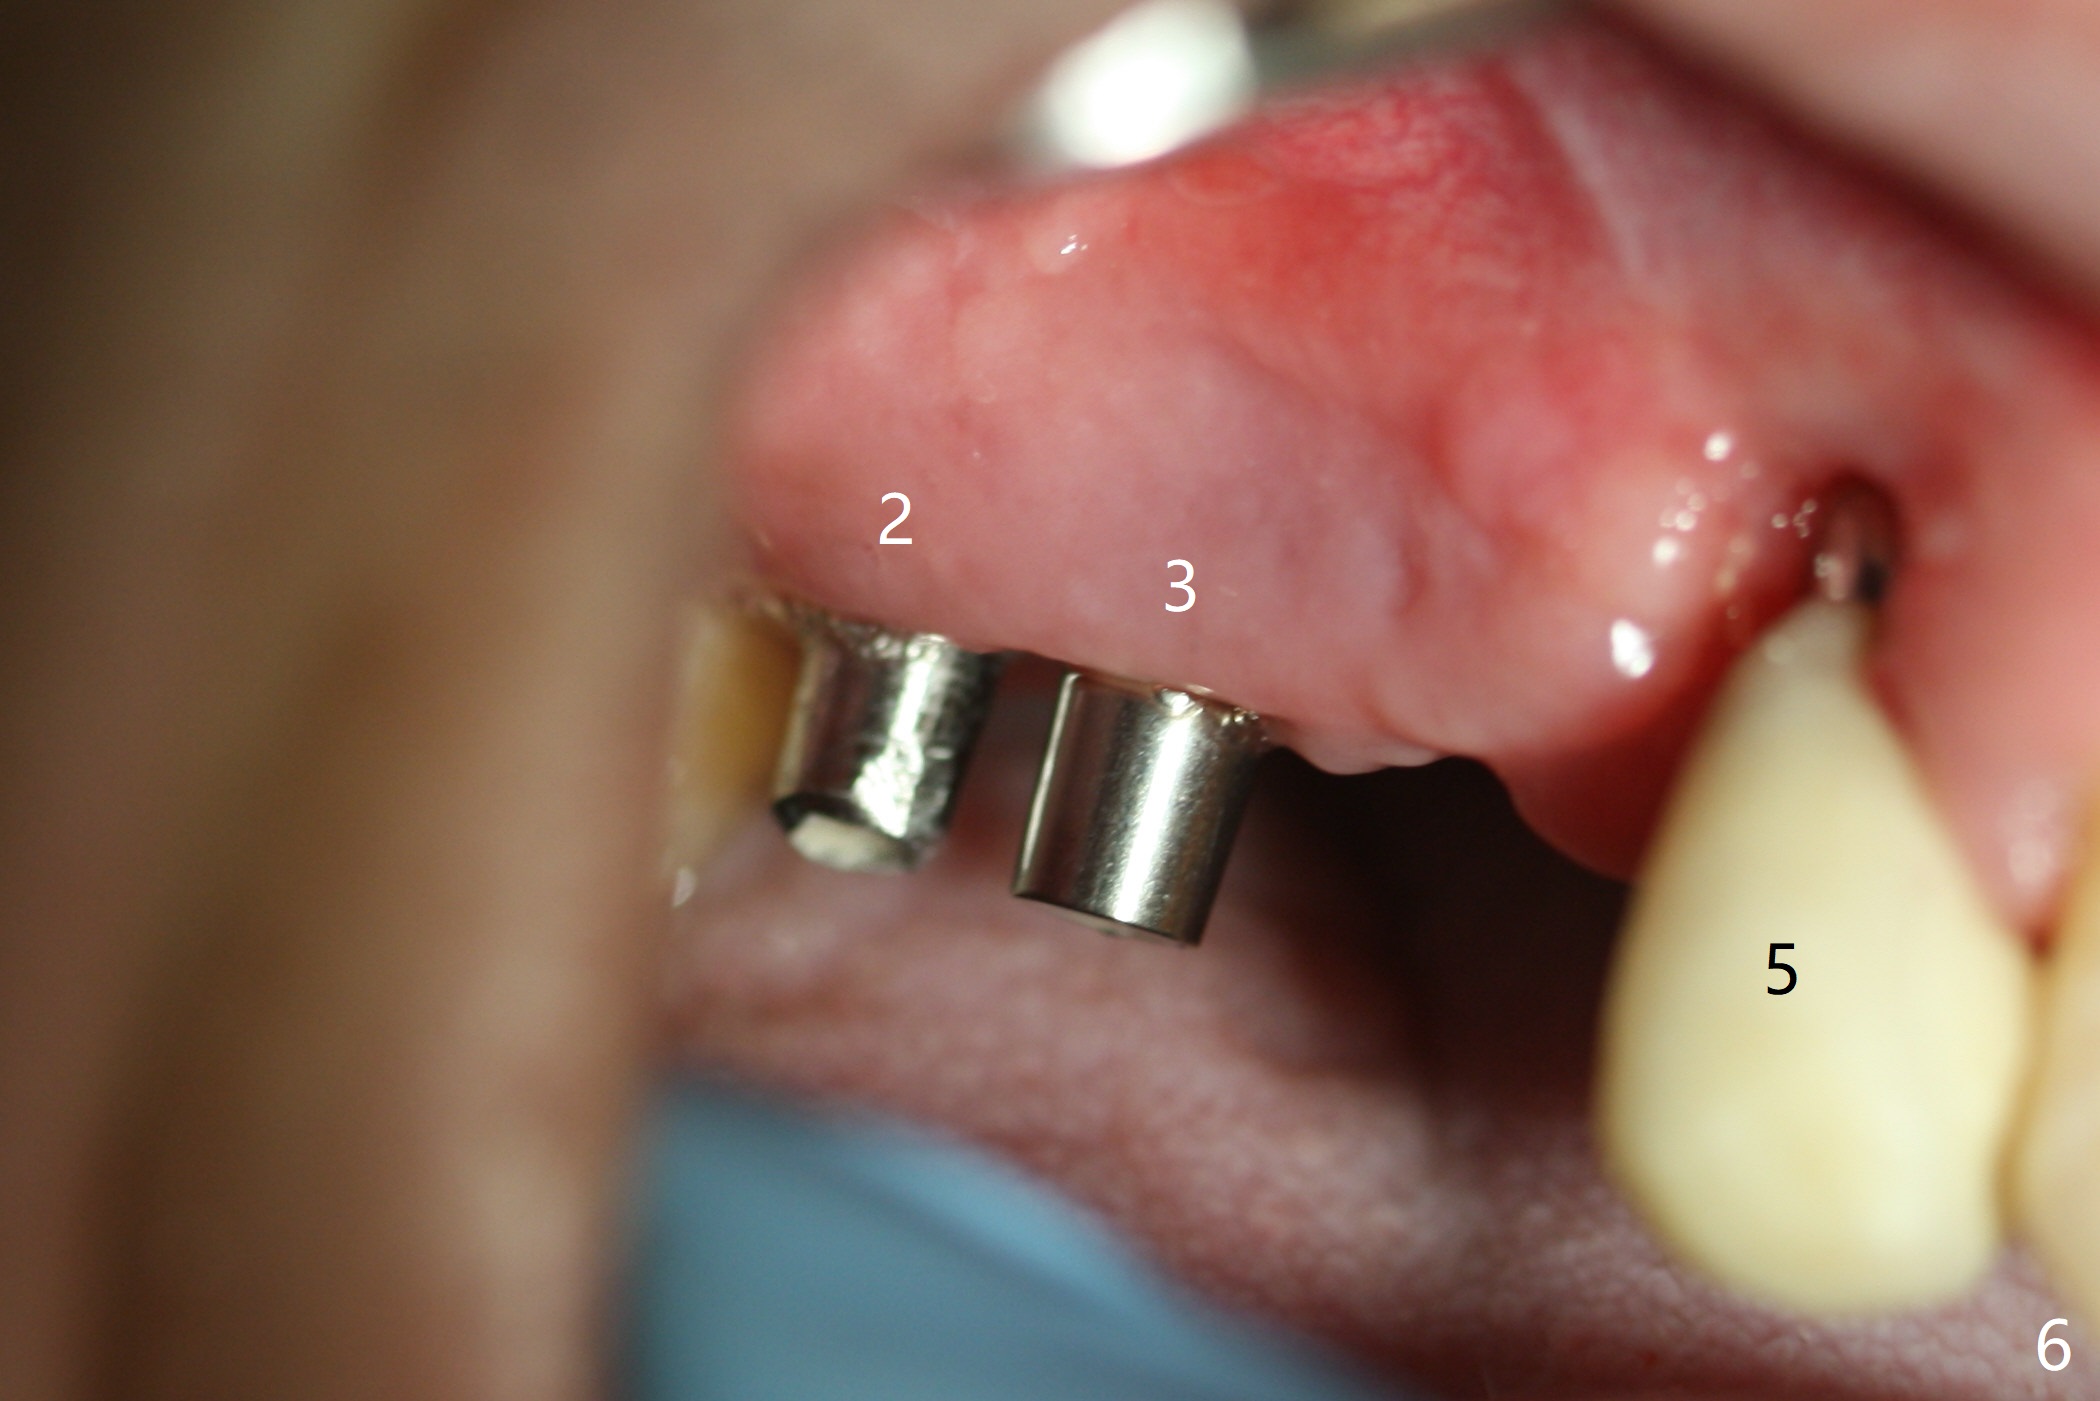

After extraction, the depths of initial osteotomy at #2, 3 and 5 are 13, 11.5 and 10 mm, respectively (Fig.1). Following adjustment of trajectory, a 3.8x13 mm UF implant is placed at #5 (Fig.2) with insertion of a 4.5x2 mm mill abutment as well as mineralized cortical/cancellous allograft (Vanilla, *). The mill abutment is chosen because the margin of a 5.5x7(5) mm cemented abutment is severely subgingival (Fig.4 at #3; ^ gingival margin). By the same token, a 4.5x3 mm mill abutment is placed at #2. In fact all of the 3 implants are placed 2-3 mm out of the bone (Fig.5). To prevent periimplantitis, abundant allograft is placed around the implants/abutments (Fig.2,4 *). Nearly 2 months postop, the mill abutment at #2 is adjusted for its height, while a 5.5x2.5 mm mill abutment is placed at #3 (Fig.6). To regain the buccal gingiva, the buccal margin of the provisional is shortened (Fig.6,7). Two weeks later, the gingival regrowth is not obvious (Fig.8 (nearly 3 months postop)). Local poor oral hygiene remains. A provisional FPD is fabricated. If his occlusion is normal for another 2 weeks, impression will be taken for upper (or UL) permanent restoration.